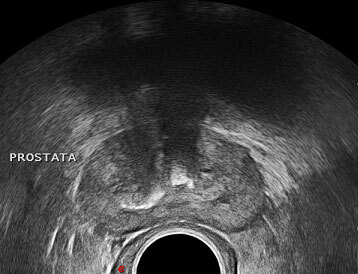

¿Qué prueba se usa para el estudio de próstata?

¿Qué se puede visualizar en esta ecografía?